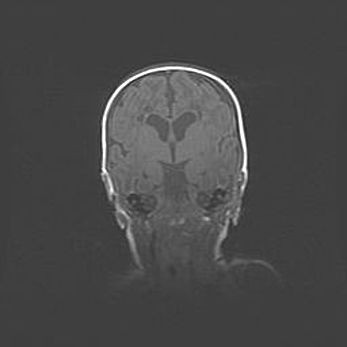

Множественные кисты обоих полушарий головного мозга, наибольшая из них в правой затылочной области. Ассиметричная атрофическая гидроцефалия.

Возраст: 7 месяцев

Вес: 5660 г

Пол: мужской

Окружность головы: 41,5 см

Срок гестации: 28-29 недель

Кисты головного мозга развиваются в результате многоочаговых некрозов вещества мозга и возникают вследствие перенесенной перинатальной инфекции, менингитов, энцефалитов, асфиксии, родовой травмы, расстройств мозгового кровообращения различного генеза. Образованию кист в веществе головного мозга плодов и новорожденных способствуют такие факторы, как высокое содержание в нем воды, недостаточная (или отсутствие) миелинизация и слабая астроглиальная реакция на повреждение.

Кисты могут сочетаться с гидроцефалией и другими поражениями головного мозга.